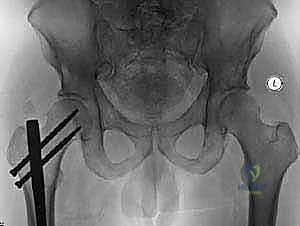

- الأشعة السينية العادية (X-rays): الخطوة الأولى والأساسية. تظهر تدمير العظم (الآفات الحالّة) أو زيادة الكثافة غير الطبيعية (الآفات التكوينية).

- التصوير المقطعي المحوسب (CT Scan): يوفر صوراً ثلاثية الأبعاد تفصيلية للعظام. يعتبر الأداة الأهم لتقييم مدى تدمير العظم القشري (الطبقة الخارجية الصلبة) وتخطيط حجم ونوع المفصل الاصطناعي بدقة.

- التصوير بالرنين المغناطيسي (MRI): يوضح مدى انتشار الورم داخل نخاع العظم وفي الأنسجة الرخوة المحيطة بالمفصل.

- المسح الذري للعظام (Bone Scan) أو مسح PET-CT: لتحديد ما إذا كانت هناك نقائل أخرى في باقي أجزاء الهيكل العظمي.